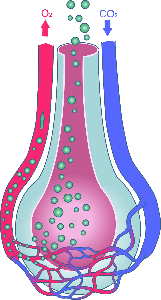

Detailreiche Fotografien aus der medizinischen Praxis ergänzen die Texte; moderne, genaue,

wissenschaftliche Zeichnungen geben Einblick in die Anatomie und die Funktion der Lunge und

anderer Organe.